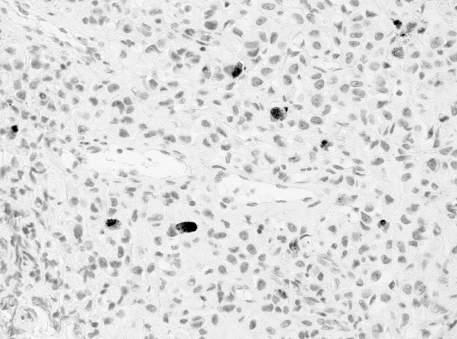

In the remaining 25/180 (13 9%) patients with absence of cancer: 1/25 (4%) had a specific granulomatous prostatitis (Mycobacterium Tubercolosis), 8/25 (32%) an aspecific granulomatous prostatitis, and 16/25 (64%) a normal parenchyma None of the patients had significant complications (only Clavien-Dindo grade I) following prostate

biopsy, requiring hospital admission The men with granulomatous prostatitis underwent specific antibiotic therapy followed by laboratory showing negative culture of urine and semen; moreover, the urine and sperm search for Mycobacterium Tuberculosis test including the semen polymerase chain reaction (PCR) (TB-PCR) were negative The clinical follow up of patients without proven diagnosis of PCa including PSMA PET/CT evaluation has been reported